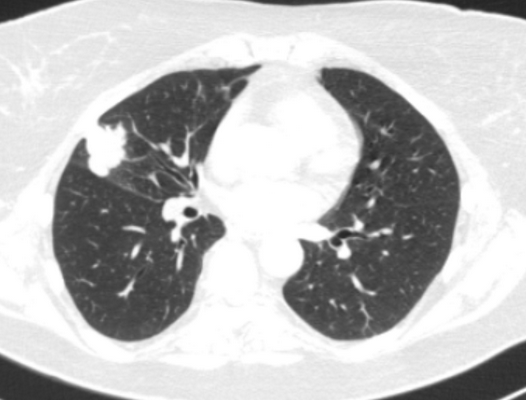

Фото 3 — Лобэктомия

Фото 4 — Пневмонэктомия

- по объему резекции (лобэктомии (удаление доли легкого), билобэктомии (удаление двух долей легкого), пневмонэктомии (удаление целого легкого)),

Лобэктомия - удаление одной содержащей опасное новообразование доли.

Билобэктомия - изъятие двух долей правого легкого.

Пульмонэктомия - полное удаление легкого. Операция может потребоваться при расположении опухоли рядом с центром грудной клетки.

- — предпочтительное и наиболее распространенное хирургическое вмешательство при раке легкого. Во время него удаляют долю органа. Анатомически правое легкое состоит из трех долей, левое — из двух долей, разделенных бороздами.

- Пневмонэктомия (пульмонэктомия) — удаление всего легкого. Такое вмешательство может быть показано при центральном раке легкого. — удаление сегмента легкого. Эту операцию также называют клиновидной резекцией, во время нее удаляют часть доли. Таким хирургическим вмешательствам отдают предпочтение, когда нужно максимально сохранить легочную ткань, если есть риск того, что она не сможет полноценно справляться со своей функцией после удаления целой доли.